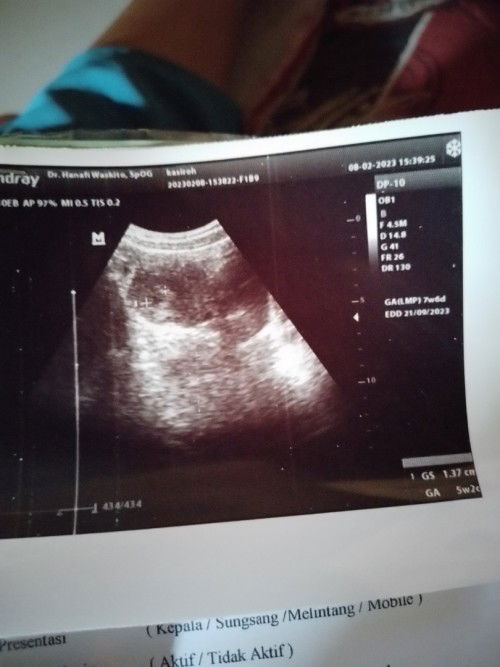

Hpht sma usg beda jauh

Bun bisa gk kta menghitung kehamila dri usg krna kalau ngikut hpht udah mau 8 sdngkn klau ikut usg bru 5w3d. Sdng suami pulng dri luar kota aja blm ada 8 mnggu